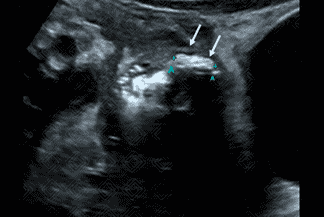

Texto alternativo para a imagem Figura 1. Créditos: Dra. Elazir Mota - Rio de Janeiro/RJ

Descrição das figuras 1 e 2: Ultrassonografia do abdome. Paciente jovem com queixa de dor na fossa ilíaca direita e febre iniciada há dois dias. Realizou ultrassonografia do abdome na emergência, evidenciando apêndice espessado, medindo 0,9 cm, não compressível e com aumento da vascularização parietal ao Doppler colorido (figura 1). Observa-se, ainda, presença de apendicolito na sua extremidade, caracterizado por imagem ecogênica com sombra acústica posterior (figura 2 - setas brancas).